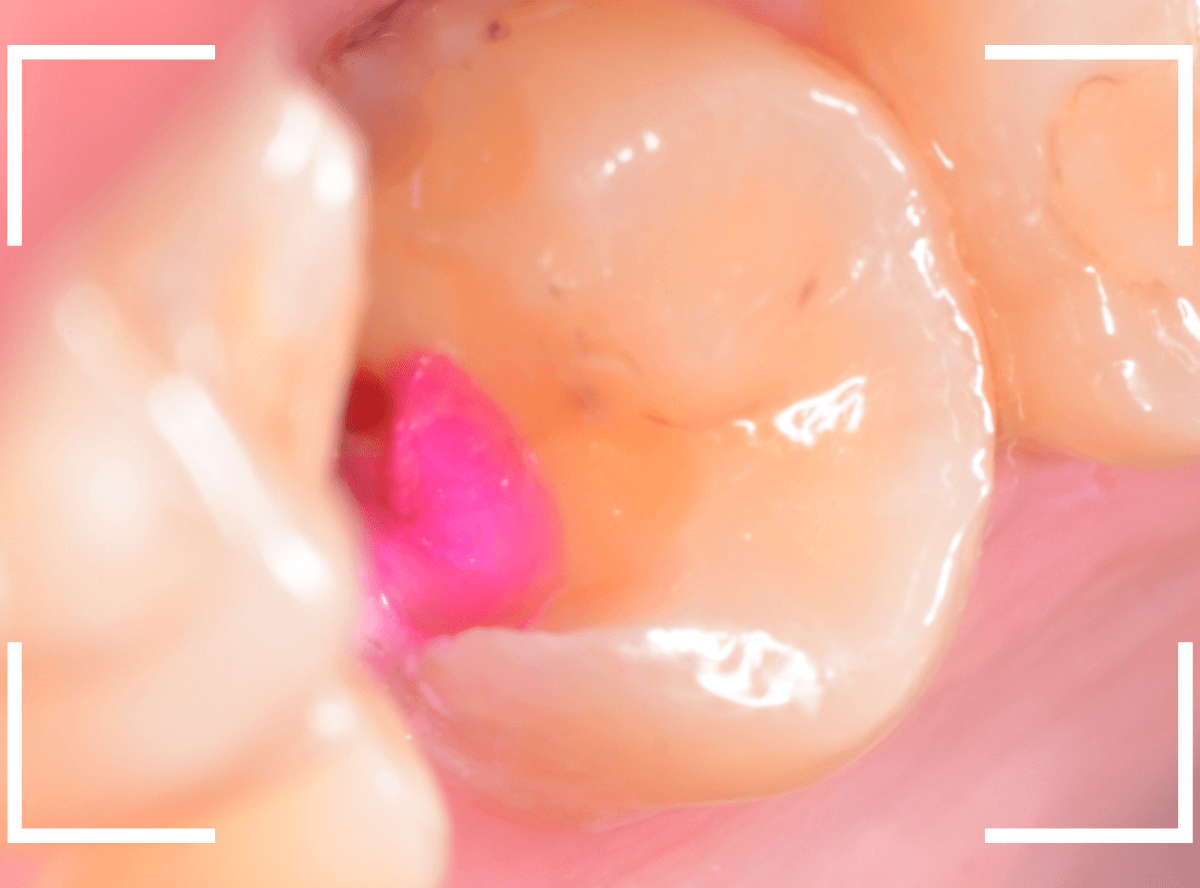

虫歯をかなり除去しところで、う蝕検知液でチェックします。

赤い部分が虫歯です。

まだ虫歯が取り切れていません。

う蝕検知液で染色されないところまで、そ~っと虫歯を除去しました。

残念ながら、歯の神経が一部露出しています。

状況的には厳しいですが、神経を保護するお薬をつめて、セメントで蓋をして、痛みが出たら、神経を除去する必要がある事を説明して経過観察することになりました。